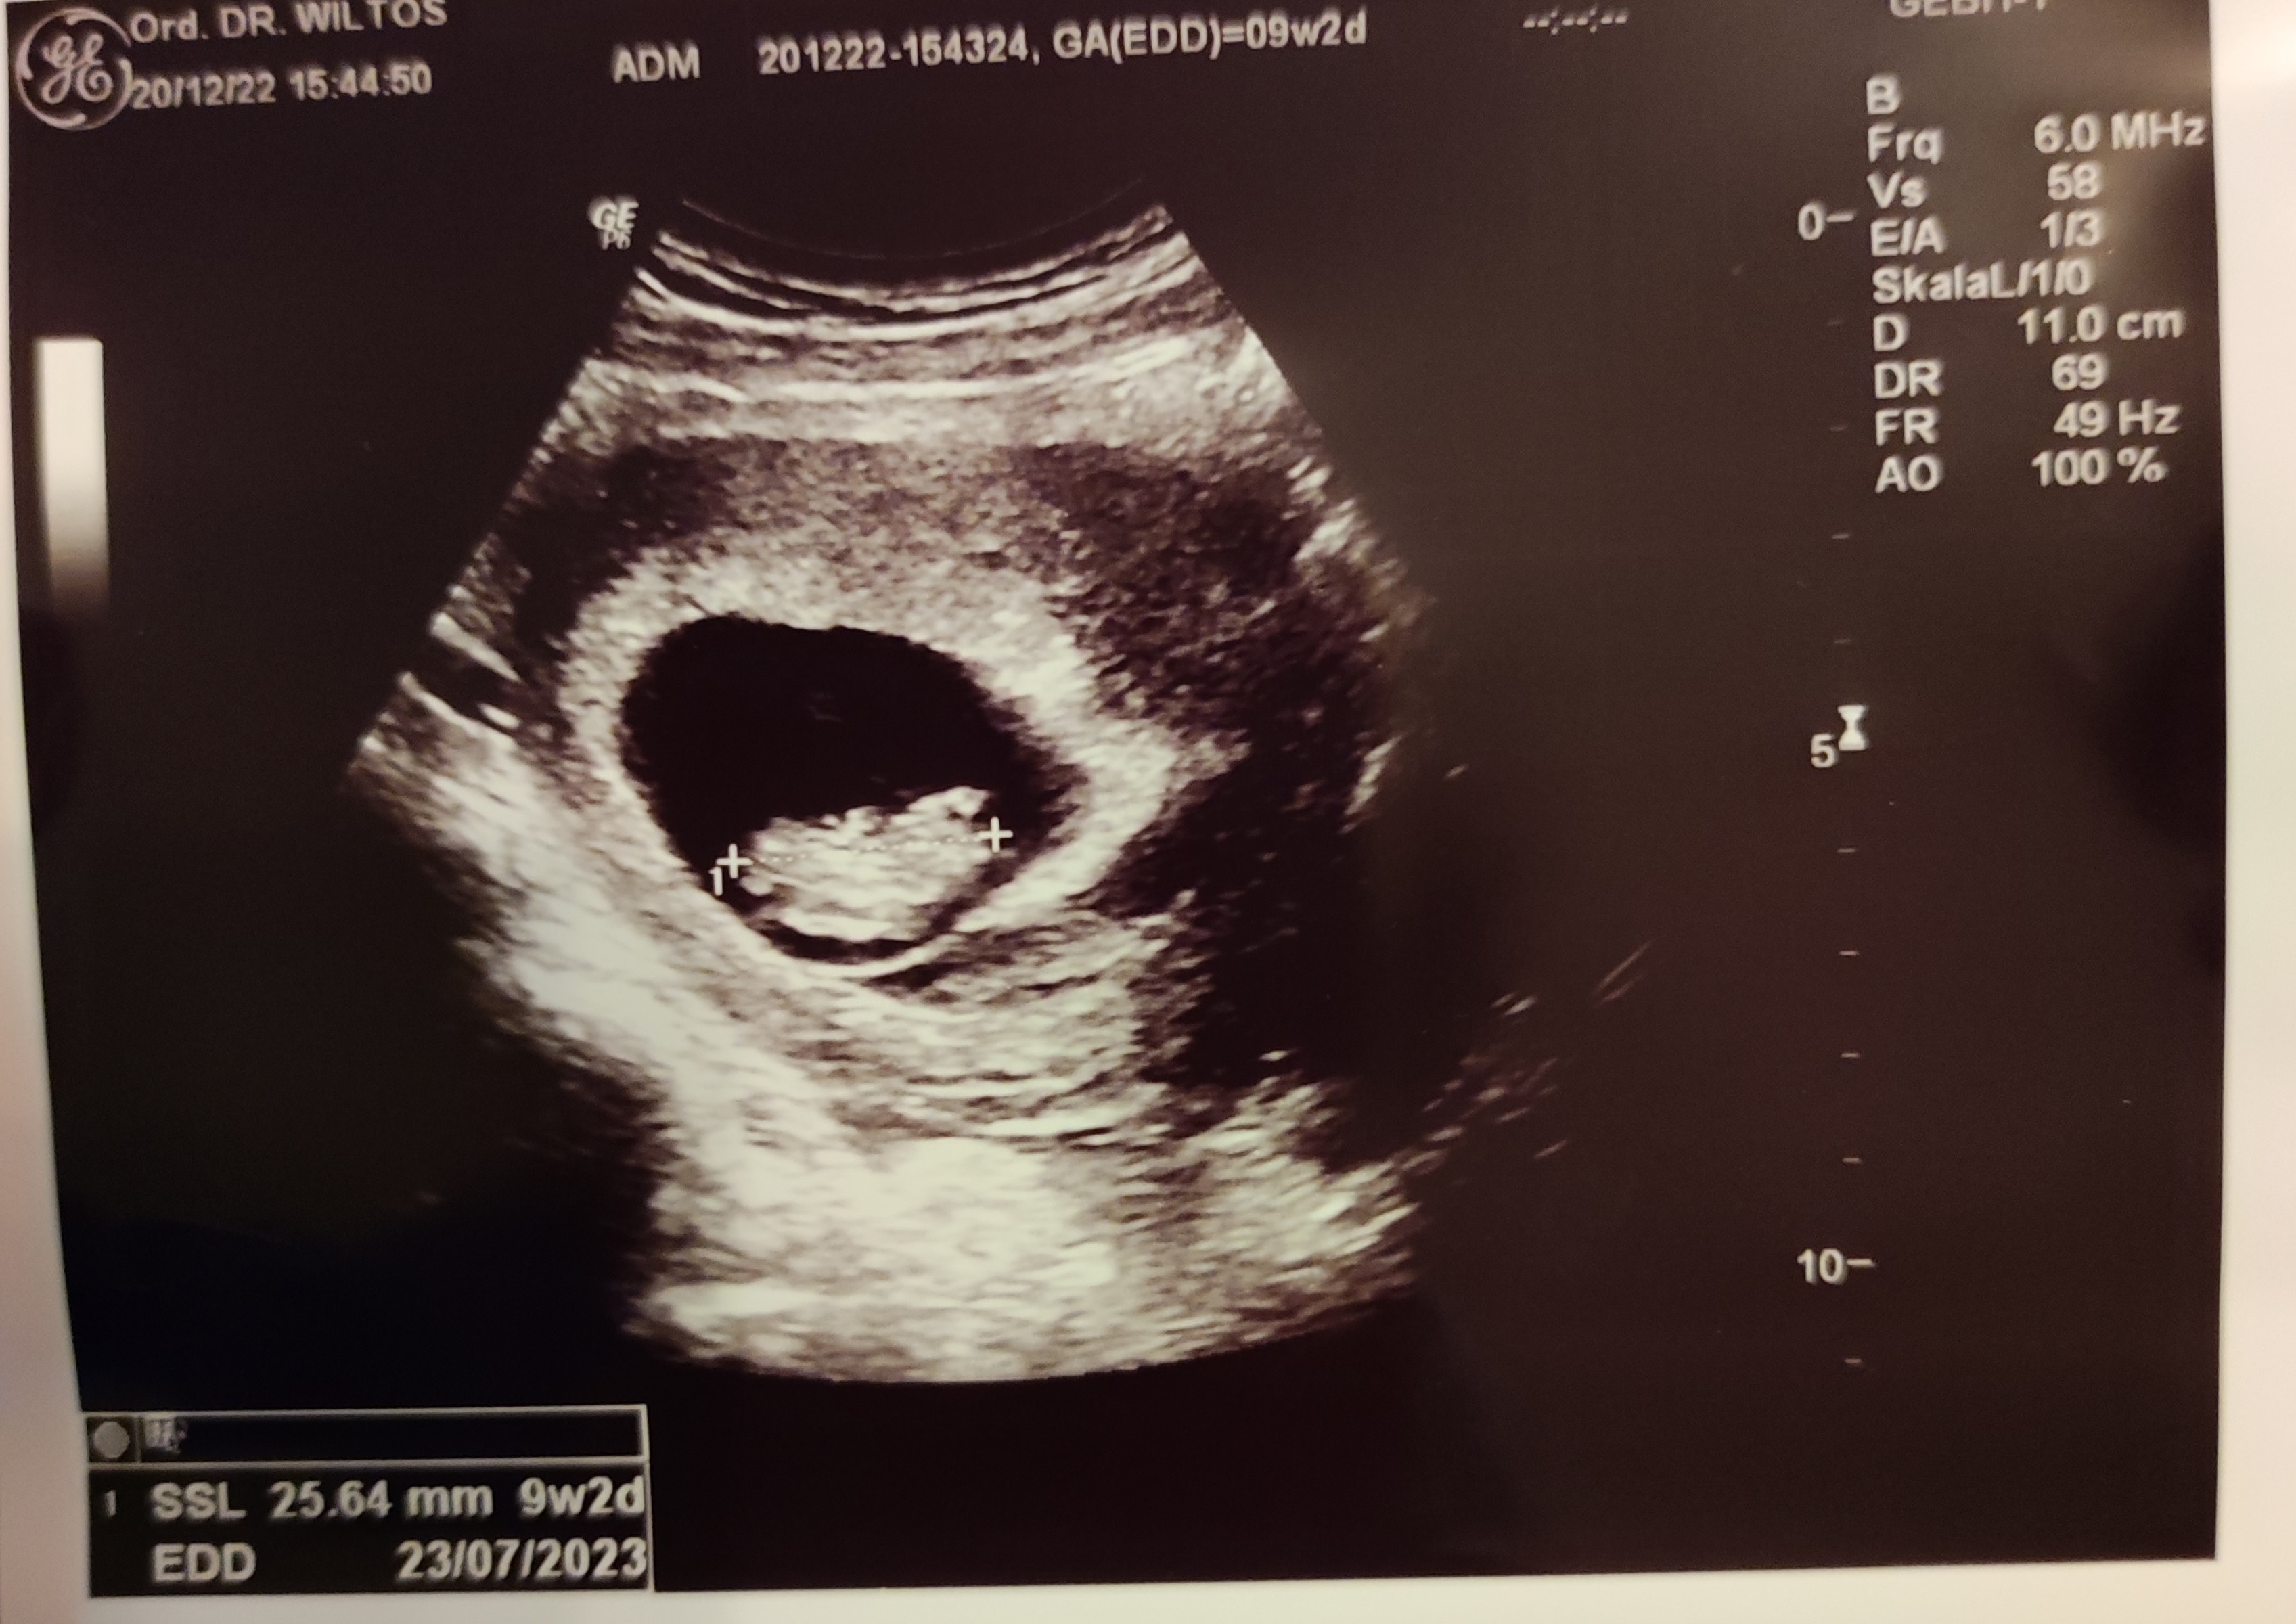

Zdjęcie nie bardzo wyraźne ale dzidzia melduje się że u niej wszystko dobrze, mamy już 2,5 cm![]()